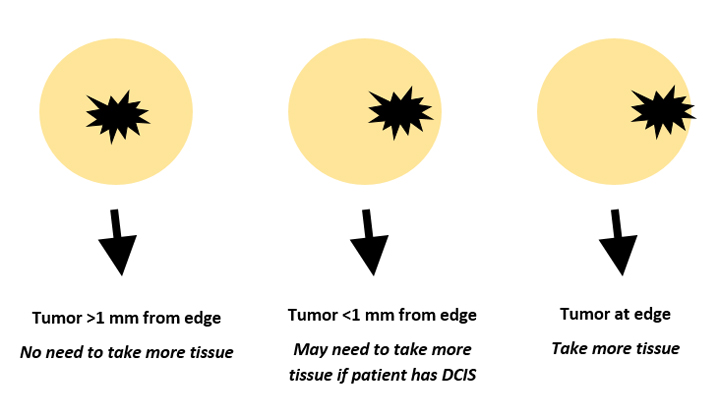

Understanding Surgical Margins In Breast Cancer

cancer margins surgical margin affect understanding ferster verywell

What Is A Clear Margin In Breast Conserving Cancer Surgery? | SpringerLink

margin conserving surgery breast cancer clear figure

Guide To Understanding Surgical Margins | KUBTEC

New Evidence About Why Clear Margins In Breast Cancer Surgery Are Such

evidence margins surgery breast cancer such clear why good

What Do Margins Mean In Breast Cancer / Resection Margin Wikipedia

dcis margins breastcancernow carcinoma ductal situ tumor stage

What are the symptoms of metastatic breast cancer?. Breast ultrasound right hypoechoic mass enhancement lobulated showing circumscribed well examination margins internal echogenicity open acoustic figure posterior shadowing lesions. What is a clear margin in breast conserving cancer surgery?